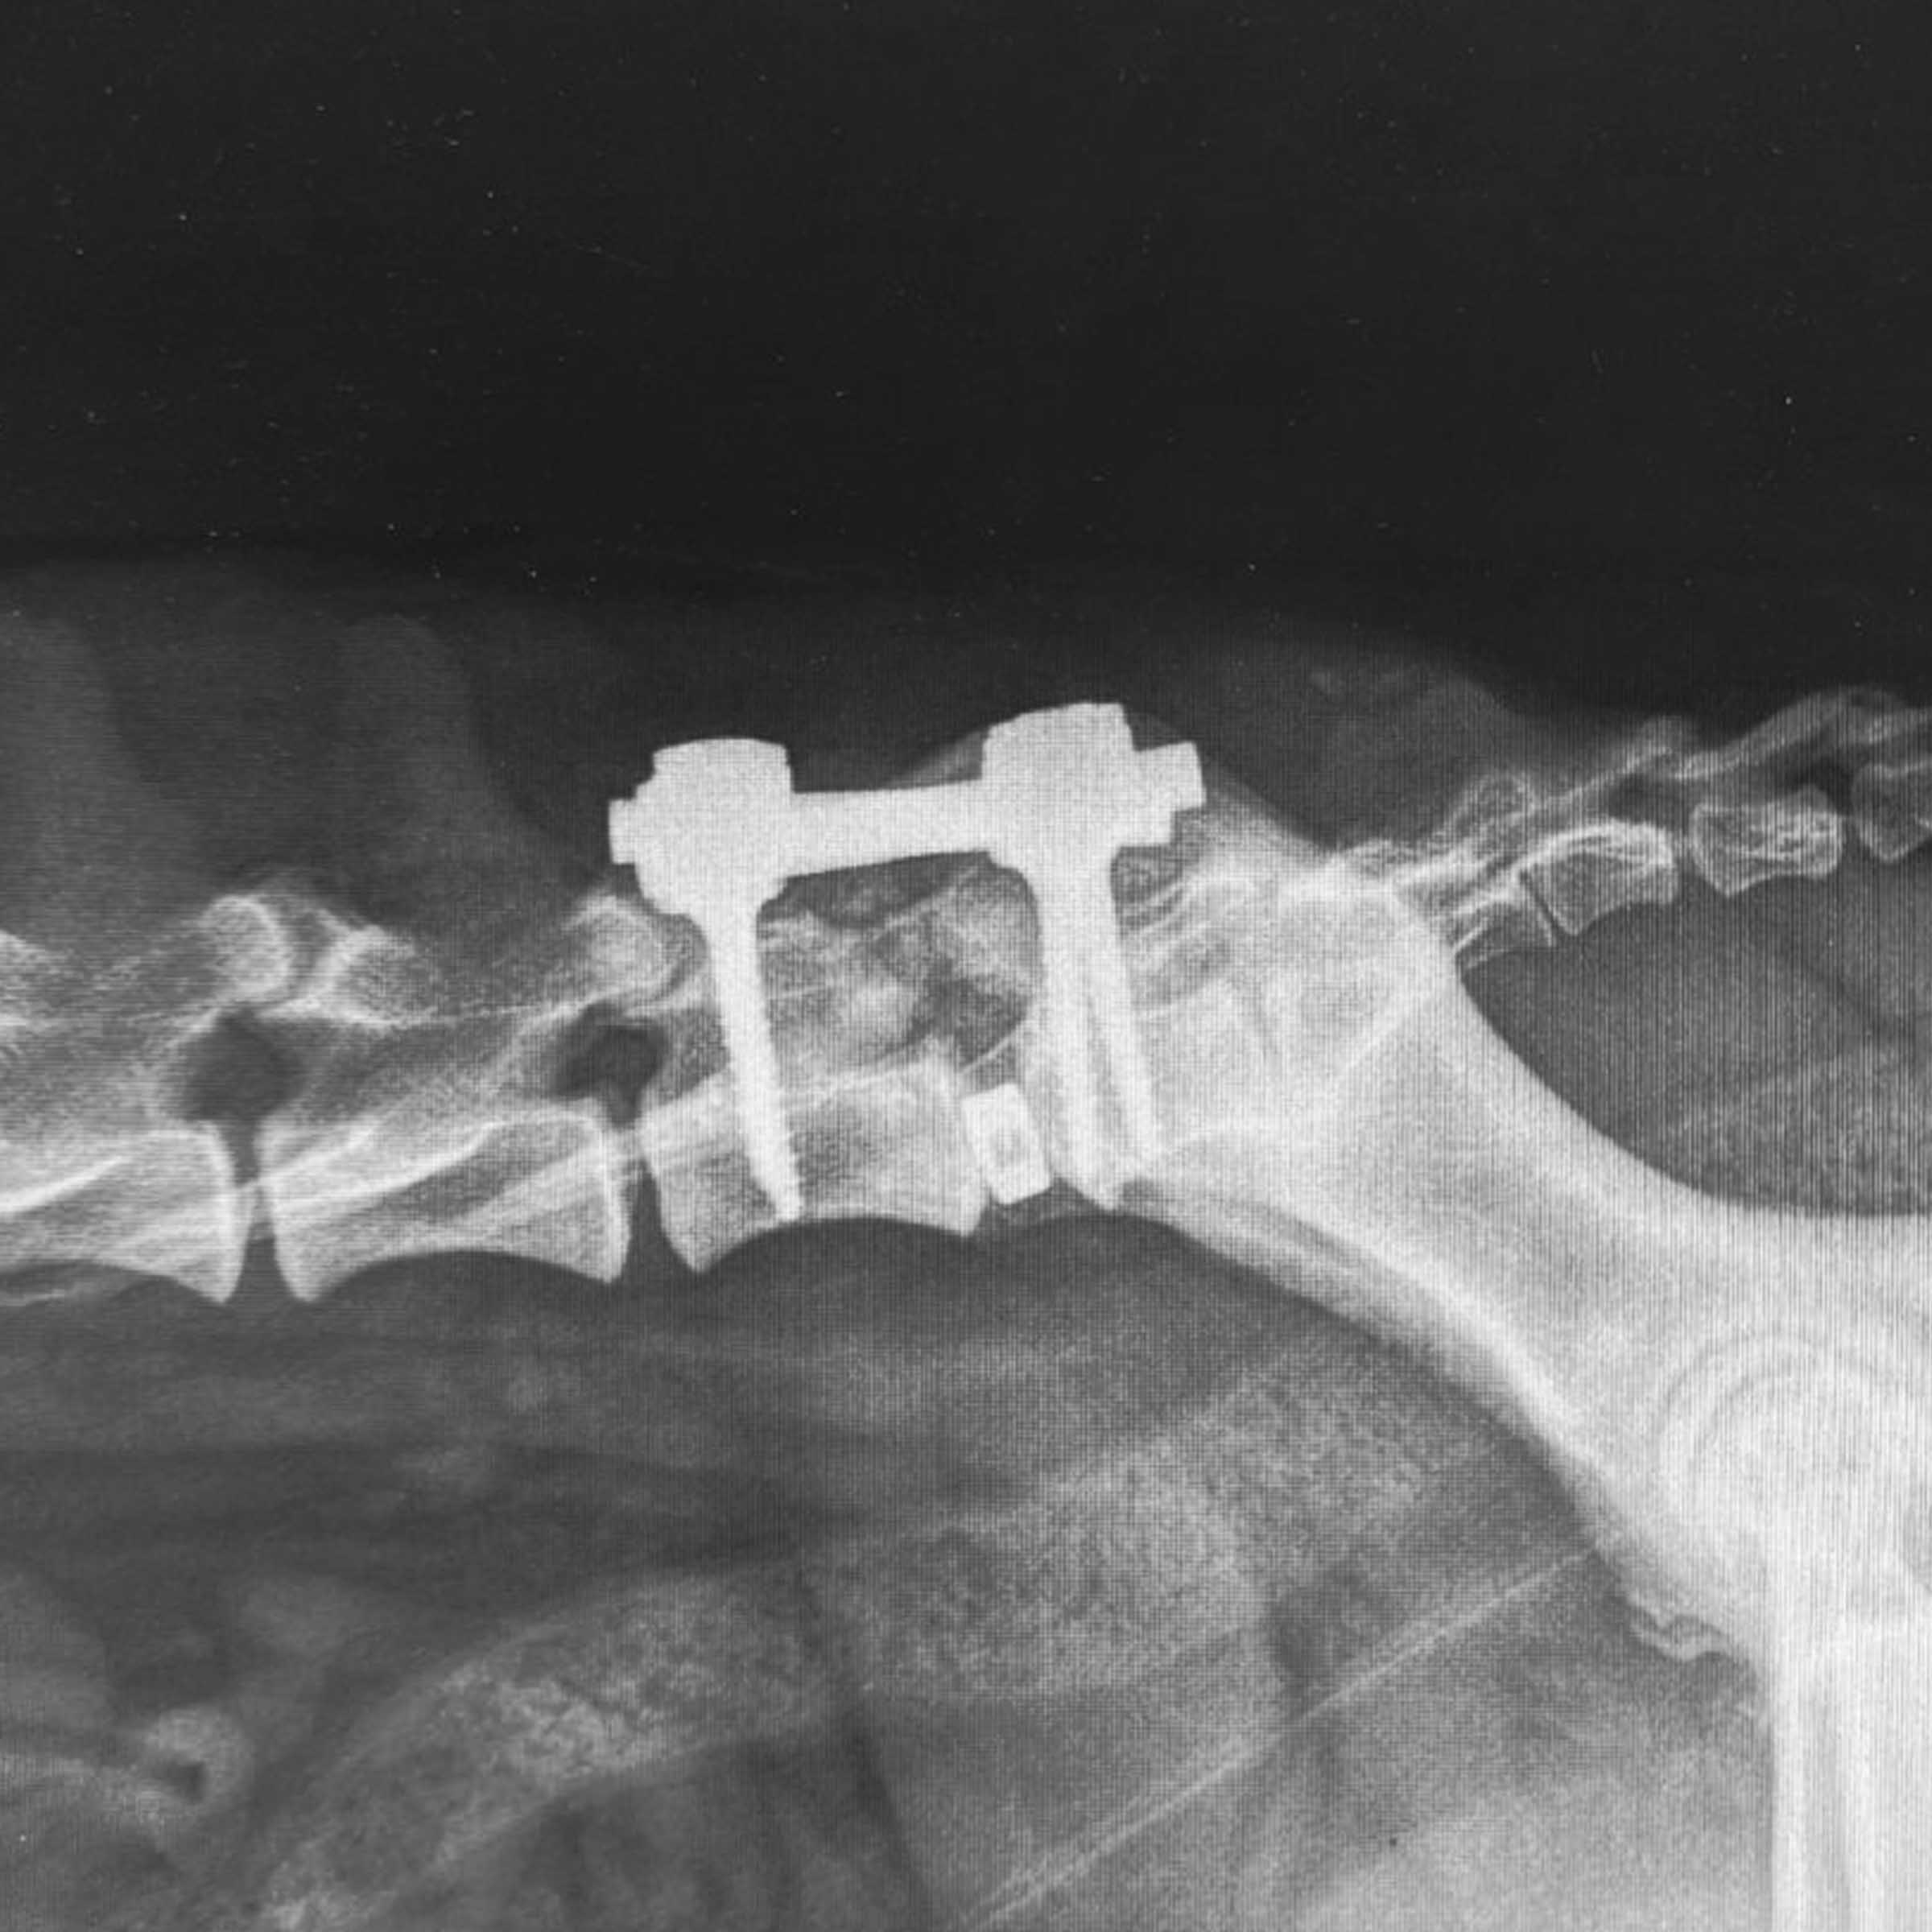

UTRECHT UNIVERSITY

Prof. Björn Meij

DVM, PhD, Dipl. ECVS

Björn Meij is a Dutch veterinarian, professor and European specialist (Diplomate ECVS) in small animal surgery since 1993.

Today, he is head of surgery at the Utrecht university where he leads a team of specialist surgeons and is ECVS resident coordinator.

Dr. Meij is well-known for his research within orthopaedics and neurosurgery.